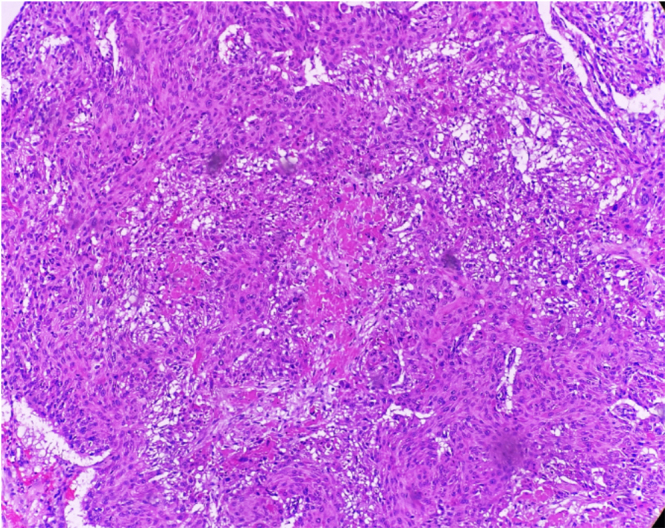

Case presentation: A 68-year-old Pakistani male with a prior diagnosis of LSCC presented with new-onset generalized tonic-clonic seizures. He had previously undergone total laryngectomy, radiotherapy, and chemotherapy. Brain MRI revealed a right frontal lobe lesion with surrounding edema, consistent with a solitary metastasis. Histopathology following craniotomy confirmed metastatic squamous cell carcinoma. The patient was managed with antiepileptics and referred for palliative whole-brain radiotherapy. He and his family opted for palliative care, declining further aggressive treatment.